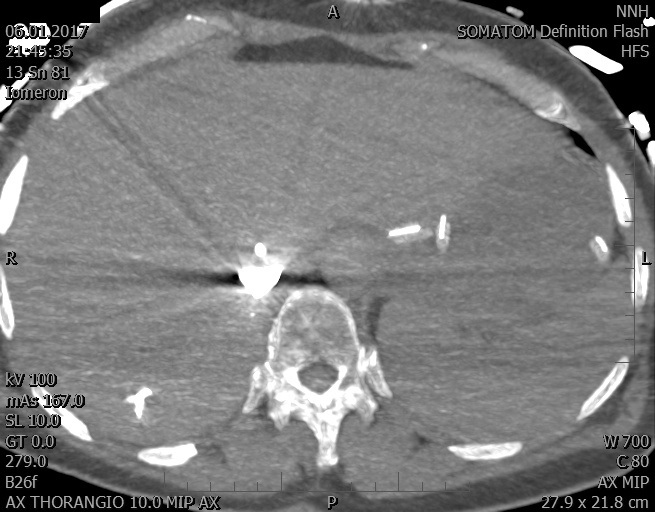

Video 2 - Echokardiograficky byla zjištěna těžká dysfunkce dilatační levé komory s nezvětšenou pravou komorou.Pro nejasnou příčinu zástavy jsme provedli i vyšetření výpočetní tomografií (CT), které vyloučilo plicní embolizaci (série 1 - soubory na konci článku). V den přijetí při přetrvávající oběhové nestabilitě byla nemocná opakovaně defibrilována pro fibrilaci komor se stabilizací rytmu po podání amiodaronu a mesocainu. Dle hemodynamických měření se jednalo o těžký kombinovaný šok. Vstupní laboratorní vyšetření bylo bez větších pozoruhodností. Posléze jsme doplnili anamnézu od příbuzných a zjistili, že pacientka užila do dvou hodin před srdeční zástavou první tabletu amoxicilinu na lehký respirační infekt. Při nevýtěžnosti vstupních vyšetření a nových anamnestických informacích jsme doplnili 14 hodin po kolapsu vyšetření koncentrace tryptázy v séru, která byla extrémně zvýšena (tabulka 2), což nás vedlo k podezření na anafylaxi.